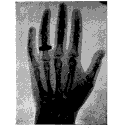

Manuel de radioscopie et de radiographie par l'emploi des rayons X